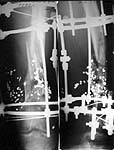

And a case to continue the discussion.

A male 31 y.o. referred to us from elsewhere after 7.5 months of external fixation after a buck-shot femoral fracture (see attachment). At the moment ther is no sign of infection either pin tract or wound. Knee ROM is 20 degrees. Walks with one cane. We think about conversion to a closed interlocked nail. I'd like to hear opinions of the group.